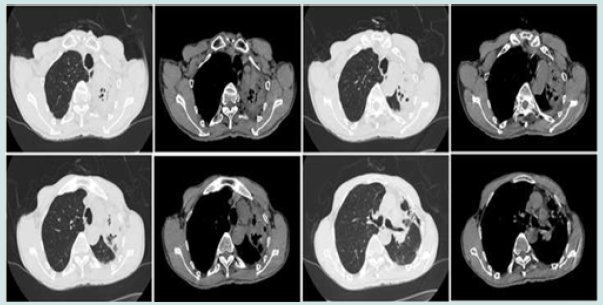

On 7 June 2021, the patient was referred to our department and underwent relevant examinations. Physical examination showed good healthy condition, but the lesion was solidly enhanced compared to the previous CT (Figure 2). Combined with the patient’s previous examination results, he was diagnosed with left CPA. The patient was unable to undergo surgical resection due to adhesions in the chest wall and poor lung function. We decided to infuse amphotericin-B into the left upper lesion under the guidance of R-EBUS. First, the bronchoscope was passed through the nasal approach into the trachea and local anaesthesia was performed by injecting 2% lidocaine (<15 ml) into the trachea/right and left bronchi through a bronchoscopic biopsy forceps. A white secretion from the posterior segment of the left upper lobe tip (Figure 3A) is flushed and cleaned. Then, a sterile catheter was placed into the tip of the left upper lobe of the lung with a guide wire and secured in the bronchus with a rubber plug under R-EBUS guidance (Figures 3B & 3C). Prior to administration, we reconfirmed that the position of the catheter had not moved by direct auscultation or CT. Then 5 mg of amphotericin B was dissolved in 10 ml of saline and injected into the left bronchus via the catheter within 5 minutes. The same dose of drug was administered once daily for four days. The catheter and rubber plug were removed after the fourth intrabronchial instillation of amphotericin B. A total of 20 mg of amphotericin B was administered during the treatment period and oral voriconazole was continued after discharge.

Figure 2: After 1 month of oral voriconazole, preoperative CT examination showing left upper lobe bronchiectasis with obstructive atelectasis and inflammation. The upper left pleura was thickened.